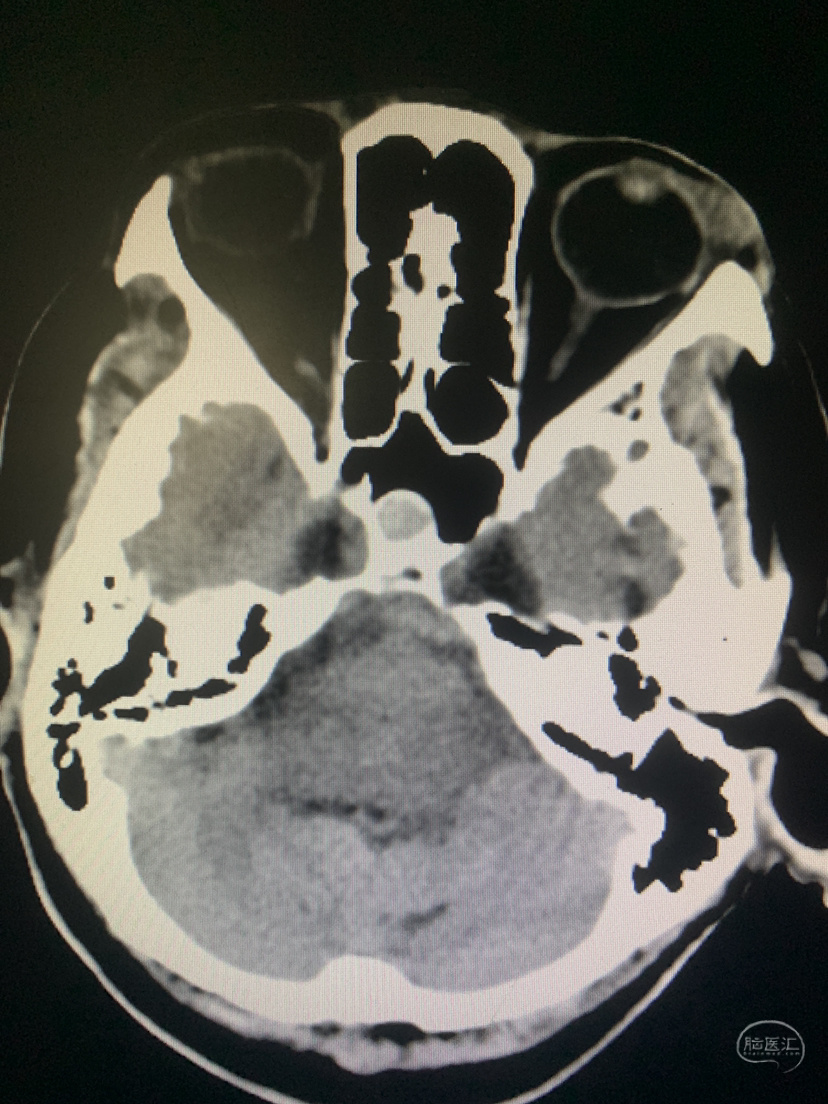

术前CT

术前CT